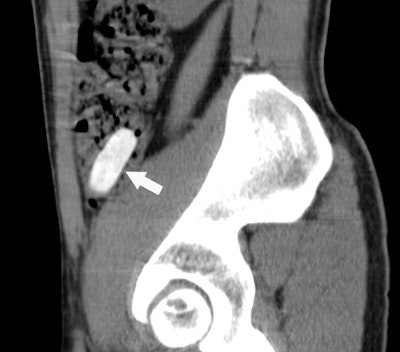

Residual cocaine-filled packet found in the cecum of a 33-year-old body packer. Abominal x-ray of the lower abdomen (above) shows no clear abnormality, whereas sagittal CT reformatted image (below) clearly depicts a dense packet (arrow), located in the cecum. Note that even in retrospect, the packet is still not visible on AXR. All images courtesy of Dr. Pascal Rousset.